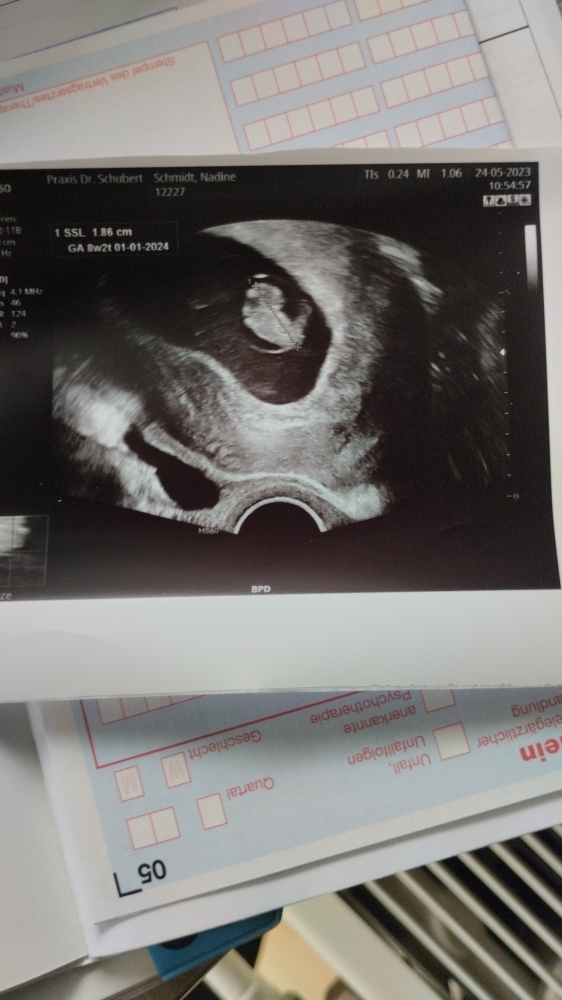

Ich bin in der 9 SSW , bin 43 Jahre alt . Mein Frauenarzt redet von einer Risikoschwangerschaft . Und meint hätte eine trisomie Gefahr . In 4 Wochen habe ich die Nackenfaltenmessung . Eine Freundin sagt Baby sieht normal aus auf dem Ultraschall Foto .was meint ihr ?

Und alleine von einem Bild in der 9 ssw kann man als Laie absolut garnichts beurteilen.